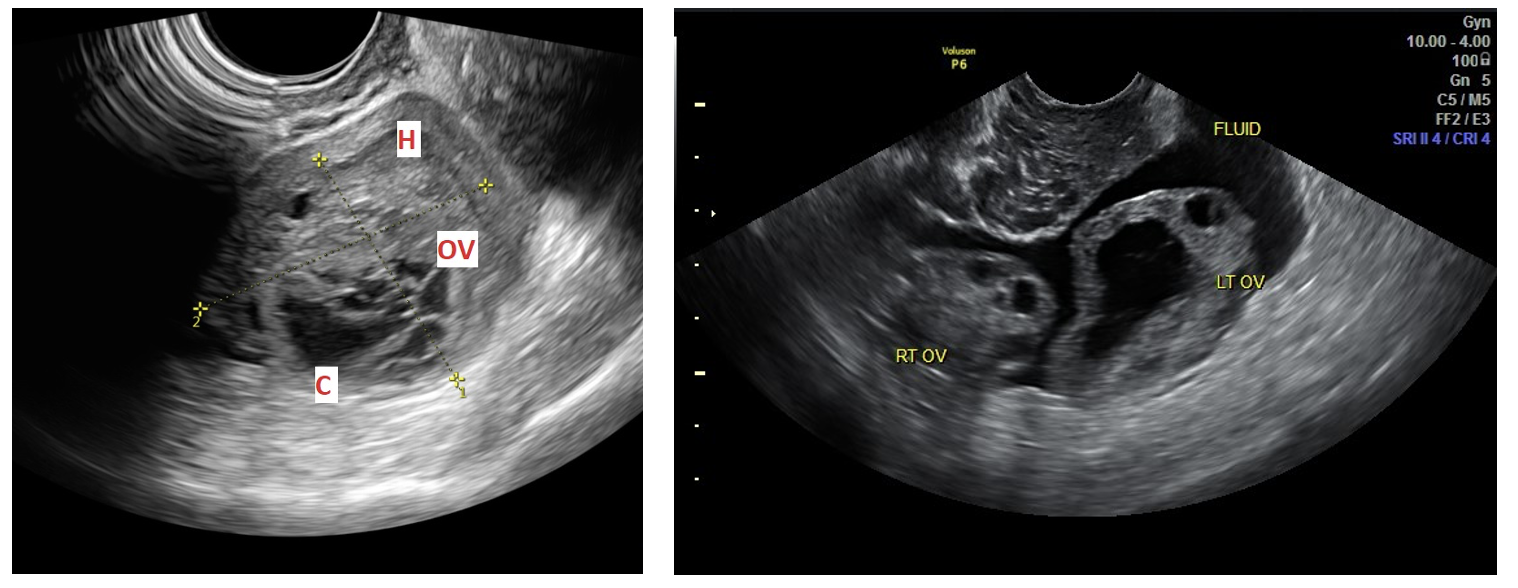

First-line imaging (per ACOG):

Pelvic ultrasound is the initial test for suspected adnexal masses.

Use both transabdominal and transvaginal views to assess for masses or free fluid.

Ultrasound technique tips (radiology-performed is current gold standard for ovarian pathology other than ectopic, this may change in the practice environment as ultrasound skills continue to grow within the ER community over the next 5-10 years):

Transabdominal → best with a full bladder.

Transvaginal → best after bladder emptying.

Color Doppler → helpful if concerned for ovarian torsion or ectopic pregnancy.

Ultrasound appearance of cysts:

Simple cysts: thin-walled, anechoic, no septations.

Complex cysts: multilocular, thickened walls, mixed solid/cystic components.

Ultrasound with color Doppler (transabdominal + transvaginal).

Common US findings:

Enlarged ovary.

Midline positioning of ovary.

Peripheral displacement of follicles.

Pelvic free fluid.